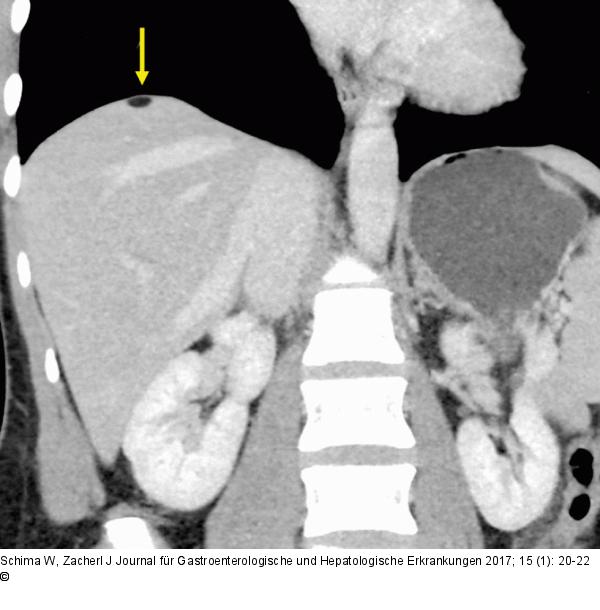

Abbildung 1c: Leberkapsel Die coronale CT-Rekonstruktion zeigt, dass die fetthältige Läsion nicht intraparenchymatös gelegen ist, sondern der Leberkapsel aufsitzt (Pfeil). |

Die coronale CT-Rekonstruktion zeigt, dass die fetthältige Läsion nicht intraparenchymatös gelegen ist, sondern der Leberkapsel aufsitzt (Pfeil). |